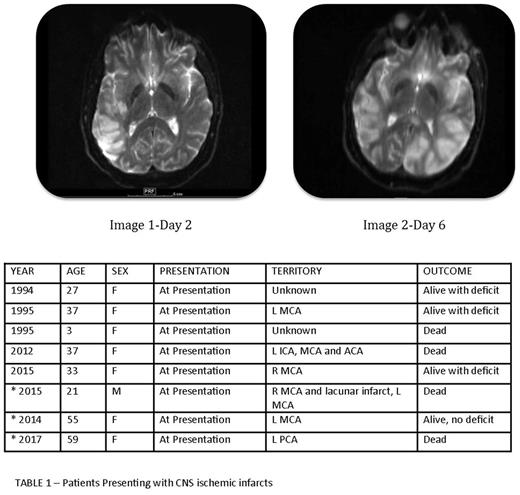

Patient 1- 21-year-old male who presented to an outlying hospital with expressive aphasia. MRI scan showed large right temporoparietal infarction. Labs showed WBC 21.6, platelets 9,000, low fibrinogen, elevated PT and elevated d-dimer. High-risk APL was confirmed and ATRA and IV dexamethasone were started. Heparin drip was initiated to decrease risk of further ischemic insult. Worsening neurologic symptoms 4 days later led to a repeat MRI scan, which showed progressive right sided infarct and a new infarct in the left distal territory of the middle cerebral territory and expired shortly thereafter. Images 1 and 2 show infarcts on day 2 and 6 of admission.